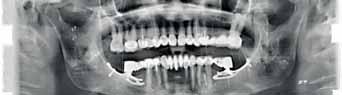

The Dental Panoramic Tomogram (DPT) confirmed the presence of all permanent teeth including the developing third molars (Figure 3). Root morphology appeared normal. The upper right central incisor had a root canal filling. The upper standard occlusal

radiograph revealed that the upper right central incisor had an adequate root filling with no periapical area. In the cephalometric assessment (Figure 4), the ANB value of 7° suggested a moderate Class II skeletal pattern. The vertical proportions were within normal values. The upper incisors were proclined at 122° and the lower incisors were of average inclination at 94°. The interincisal angle was reduced at 119°. The lower incisor to APo and the lower lip to E line were within normal limits.